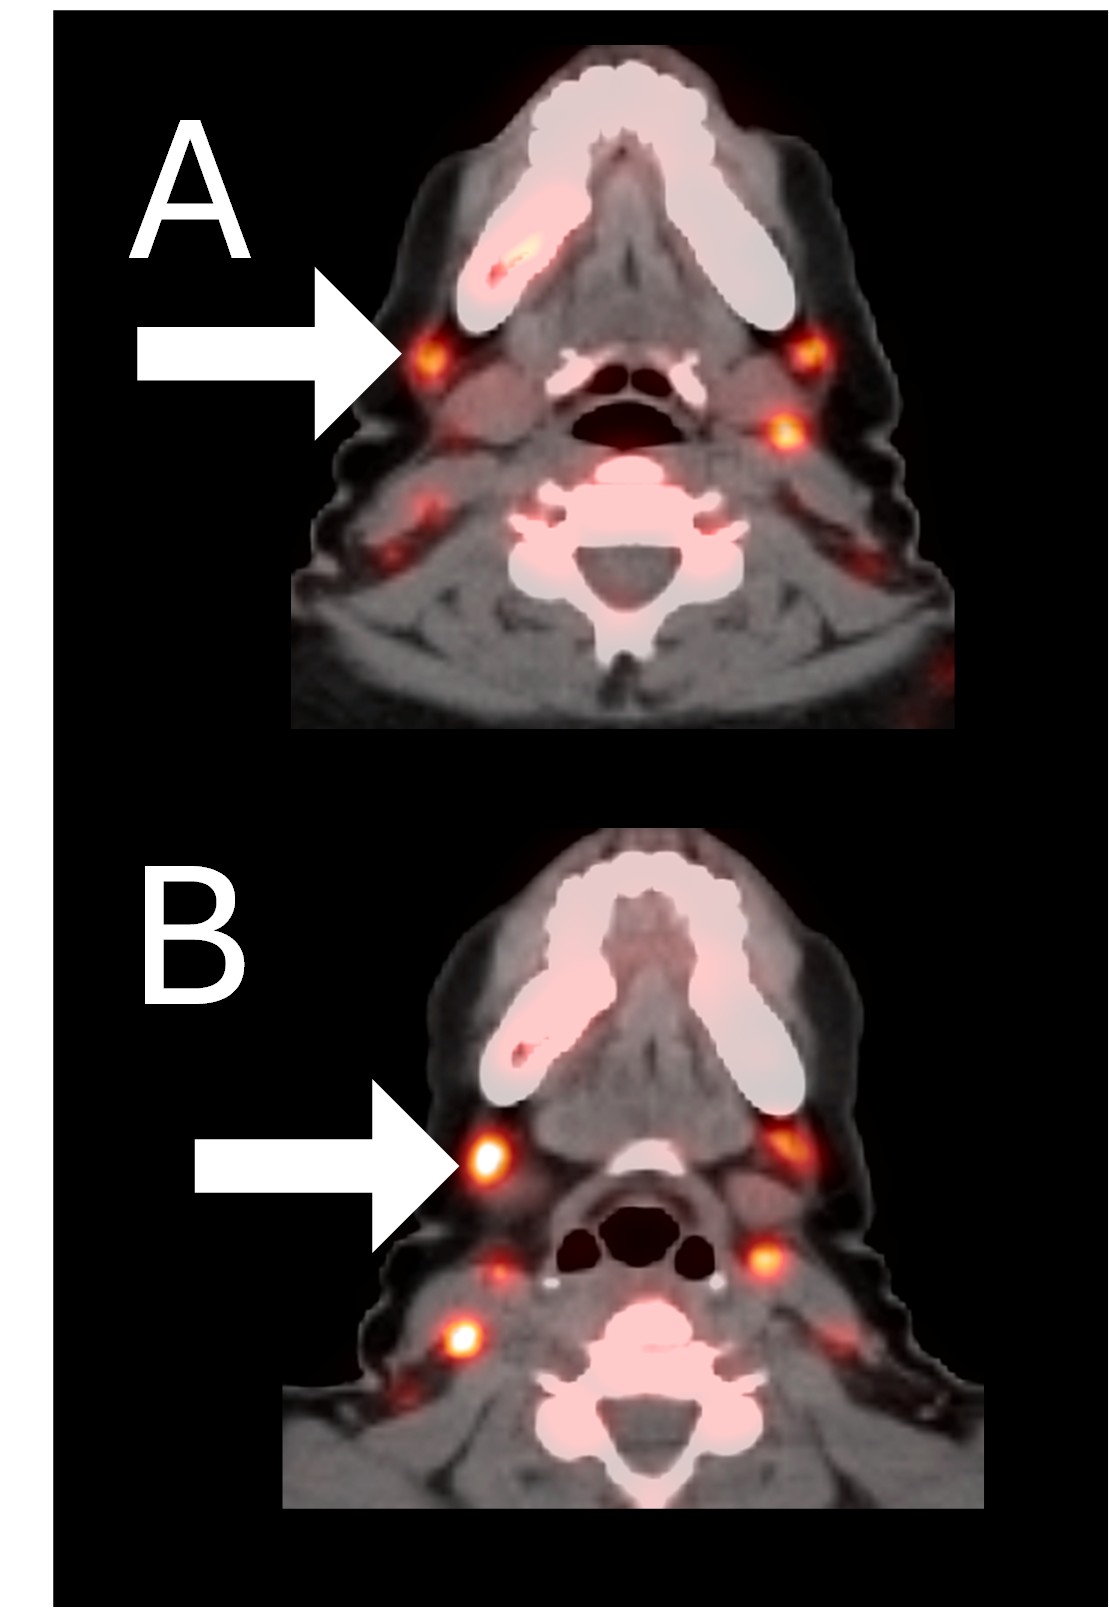

Before BriaCell Treatment Image A: CD8 ImmunoPET image

Pre-treatment imaging of cervical (neck) lymph nodes with moderate uptake indicating presence of some CD8+ cytotoxic (“killer”) T cells.

After BriaCell Treatment Image B: CD8 ImmunoPET image

Post treatment enhancement of cervical (neck) lymph nodes indicating immune system activation and increased presence of CD8+ cytotoxic T cells.

Example 2 Images (Patient 15-005): CD8 ImmunoPET images pre (A) and post (B) Bria-IMT treatment